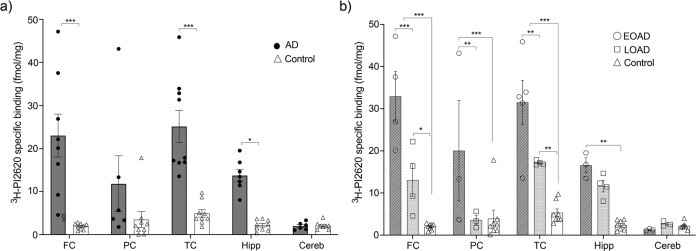

3H-PI2620 brain regional binding studies

Regional distribution studies with 3H-PI2620 (0.6 nM) were performed on homogenates from different regions of AD and control brains [FC (eight AD; nine controls); temporal cortex (TC) (nine AD; nine controls); parietal cortex (PC) (six AD; nine controls); hippocampus (seven AD; nine controls); and cerebellum (six AD; six controls)] in the presence of 1μM unlabelled PI2620 to determine NSP binding. The final steps of the experiment were carried out as described above. The AD group was then divided in Early-Onset of AD (EOAD), Late-Onset of AD (LOAD) groups. Each data point representing one case (three experiments in triplicate for each case). The data were analysed using GraphPad Prism 9 software.

3H-PI2620 regional distribution in EOAD, LOAD and control brains

The regional binding of 3H-PI2620 was analysed in five regions (FC, PC, TC, hippocampus and cerebellum) of brains from AD patients with EOAD or LOAD and controls. The results are presented in Fig. 5a, b in the FC and TC. 3H-PI2620 showed significantly higher specific binding in FC and TC (p < 0.001) as well as in hippocampus (p = 0.02) of AD brains compared to control brains (Fig. 5a).3H-PI2620 showed significantly higher specific binding in the FC (p < 0.001), PC and TC (p < 0.01) of EOAD brains than in LOAD brains. 3H-PI2620 binding was significantly higher in all cortical regions (p < 0.001) and in the hippocampus (p < 0.01) of EOAD brains than in control brains. Binding was significantly higher in LOAD brains than in controls in the FC (p = 0.02) and TC (p < 0.01) (Fig. 5b). No significant differences in 3H-PI2620 binding in the cerebellum were observed between AD and control brains.

Moreover, competition studies with different unlabelled tau tracers (MK6240 versus PI2620 for example) can generate different proportions of subpopulations of binding sites depending on which radiotracer (3H-MK6240 versus 3H-PI2620) is used in the competition studies. Although the binding sites seem to be similar for MK6240 and PI2620, they are not exactly the same (as also observed in published in silico studies; see Zhou et al. 2021 [ref. 31]). Thus, competition studies with the same unlabelled compound as the tritiated generate different binding properties that in competition studies with a different labelled compound. Our 3H-PI2620 regional distribution studies in the five regions of interest (frontal, temporal and parietal cortices, hippocampus and cerebellum) demonstrated that AD and control cases can be differentiated by 3H-PI2620, especially in the FC and TC regions (p < 0.001) and the hippocampal region (p = 0.02). This observation is in accordance with in vivo PET studies in AD and control patients [ref. 50, ref. 51]. Interestingly, when we divided the AD cases according to disease onset (EOAD before and LOAD after 65 years of age), binding of 3H-PI2620 was significantly higher in EOAD brains than in LOAD brains in the cortical regions (FC: p < 0.01, PC and TC: p < 0.01) but not in the hippocampus. The lower binding in the hippocampus could be, firstly, due to use of post-mortem brain tissue, where we target tau fibrils at the end stages of the disease and hippocampus being primarily affected regions may have been severely atrophied. Secondly, as we have discussed above, it is possible that these tracers might not target or can access all types of binding sites [ref. 28, ref. 31, ref. 52] on distinct tau tangles depending upon their morphology/conformation and maturity stages (ranging from pre-tangles to ghost tangles [ref. 53]). The 3H-PI2620 regional binding distribution followed the rank order: FC > TC > PC > hippocampus, although there was significant case-by-case variability which could be attributed to AD tau heterogeneity (with regards to folds/strains/isoforms) in different regions of the brain. A recent study by Kim et al. [ref. 36] showed that this variability could be the result of diverse structural strains of tau protein, which could dictate the rate of AD progression. They found that distinct misfolded populations of 4R-rich isomers were more prominent in rapidly pathology-driven disease. In the context of our saturation and competitive binding studies, which showed high specificity of the tracer for pathological tau, there was no significant (or potential off-target) binding in AD or control cerebellum tissue. In our previous study [ref. 21], 3H-MK6240 also displayed significantly higher binding in the cortical regions of EOAD brains, complementing the above findings that the binding behaviour and discriminative properties of 3H-PI2620 and 3H-MK6240 are comparable in AD. In vivo PET studies have also shown higher tau PET tracer binding in EOAD tissue than in LOAD tissue [ref. 54, ref. 55]. The mechanistic studies of second-generation tau tracers in primary tauopathies are still evolving and some disagreement can be observed between recently published in vivo and in vitro studies, as mentioned in the introduction [ref. 16, ref. 17, ref. 22, ref. 25–ref. 27]. This motivated us to investigate these tracers in primary tauopathies such as PSP and CBD.